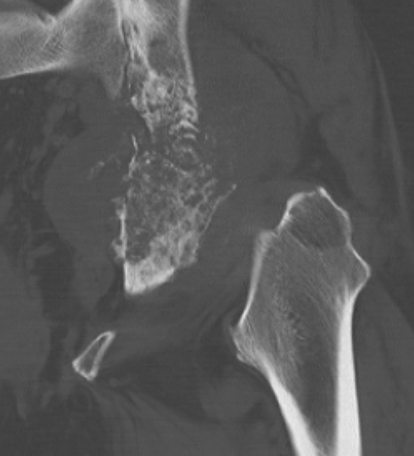

X-ray

Lytic lesion with punctate or spotty calcification

- endosteal scalloping is hallmark of chondrosarcoma

Large calcification with endosteal scalloping humerus

Large calcified lesion with endosteal scalloping